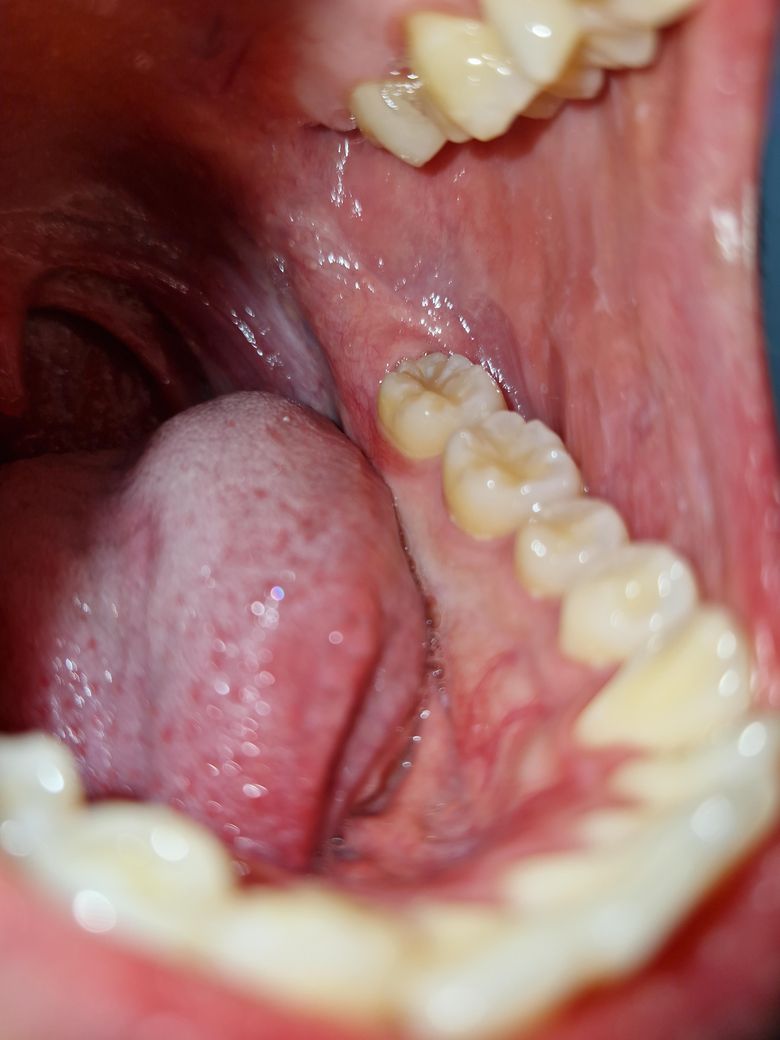

잇몸이 조금 빨갛고 말랑말랑 해진 것 같아요

어금니 쪽 잇몸 안쪽이 저렇게 빨개져있고 근처 잇몸이 약간 말랑거리는 느낌이에요. 통증이나 그런거 없고 잇몸 염증도 없었는데

어제까지 저렇게 빨갛지 않았는데 피곤해서 그런건지, 씹을 때나 양치 시에 생긴 상처같은 건지 자연 치유 될지 궁금합니다.

• 1번 째 사진